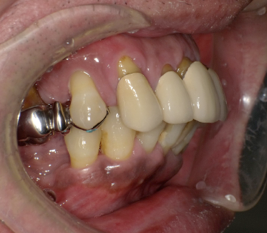

前歯に連結固定した差し歯が入っています。おそらく奥歯がなりなり、噛めなくなるので、前歯でしっかり噛めるように連結固定したのだと思いますが・・

治療前の写真です。前歯がぐらぐらになっています

奥歯がなくなり、前歯ばかりで噛んでいるとフレアーアウトといって前歯がどんどん前に傾いて出てきます。